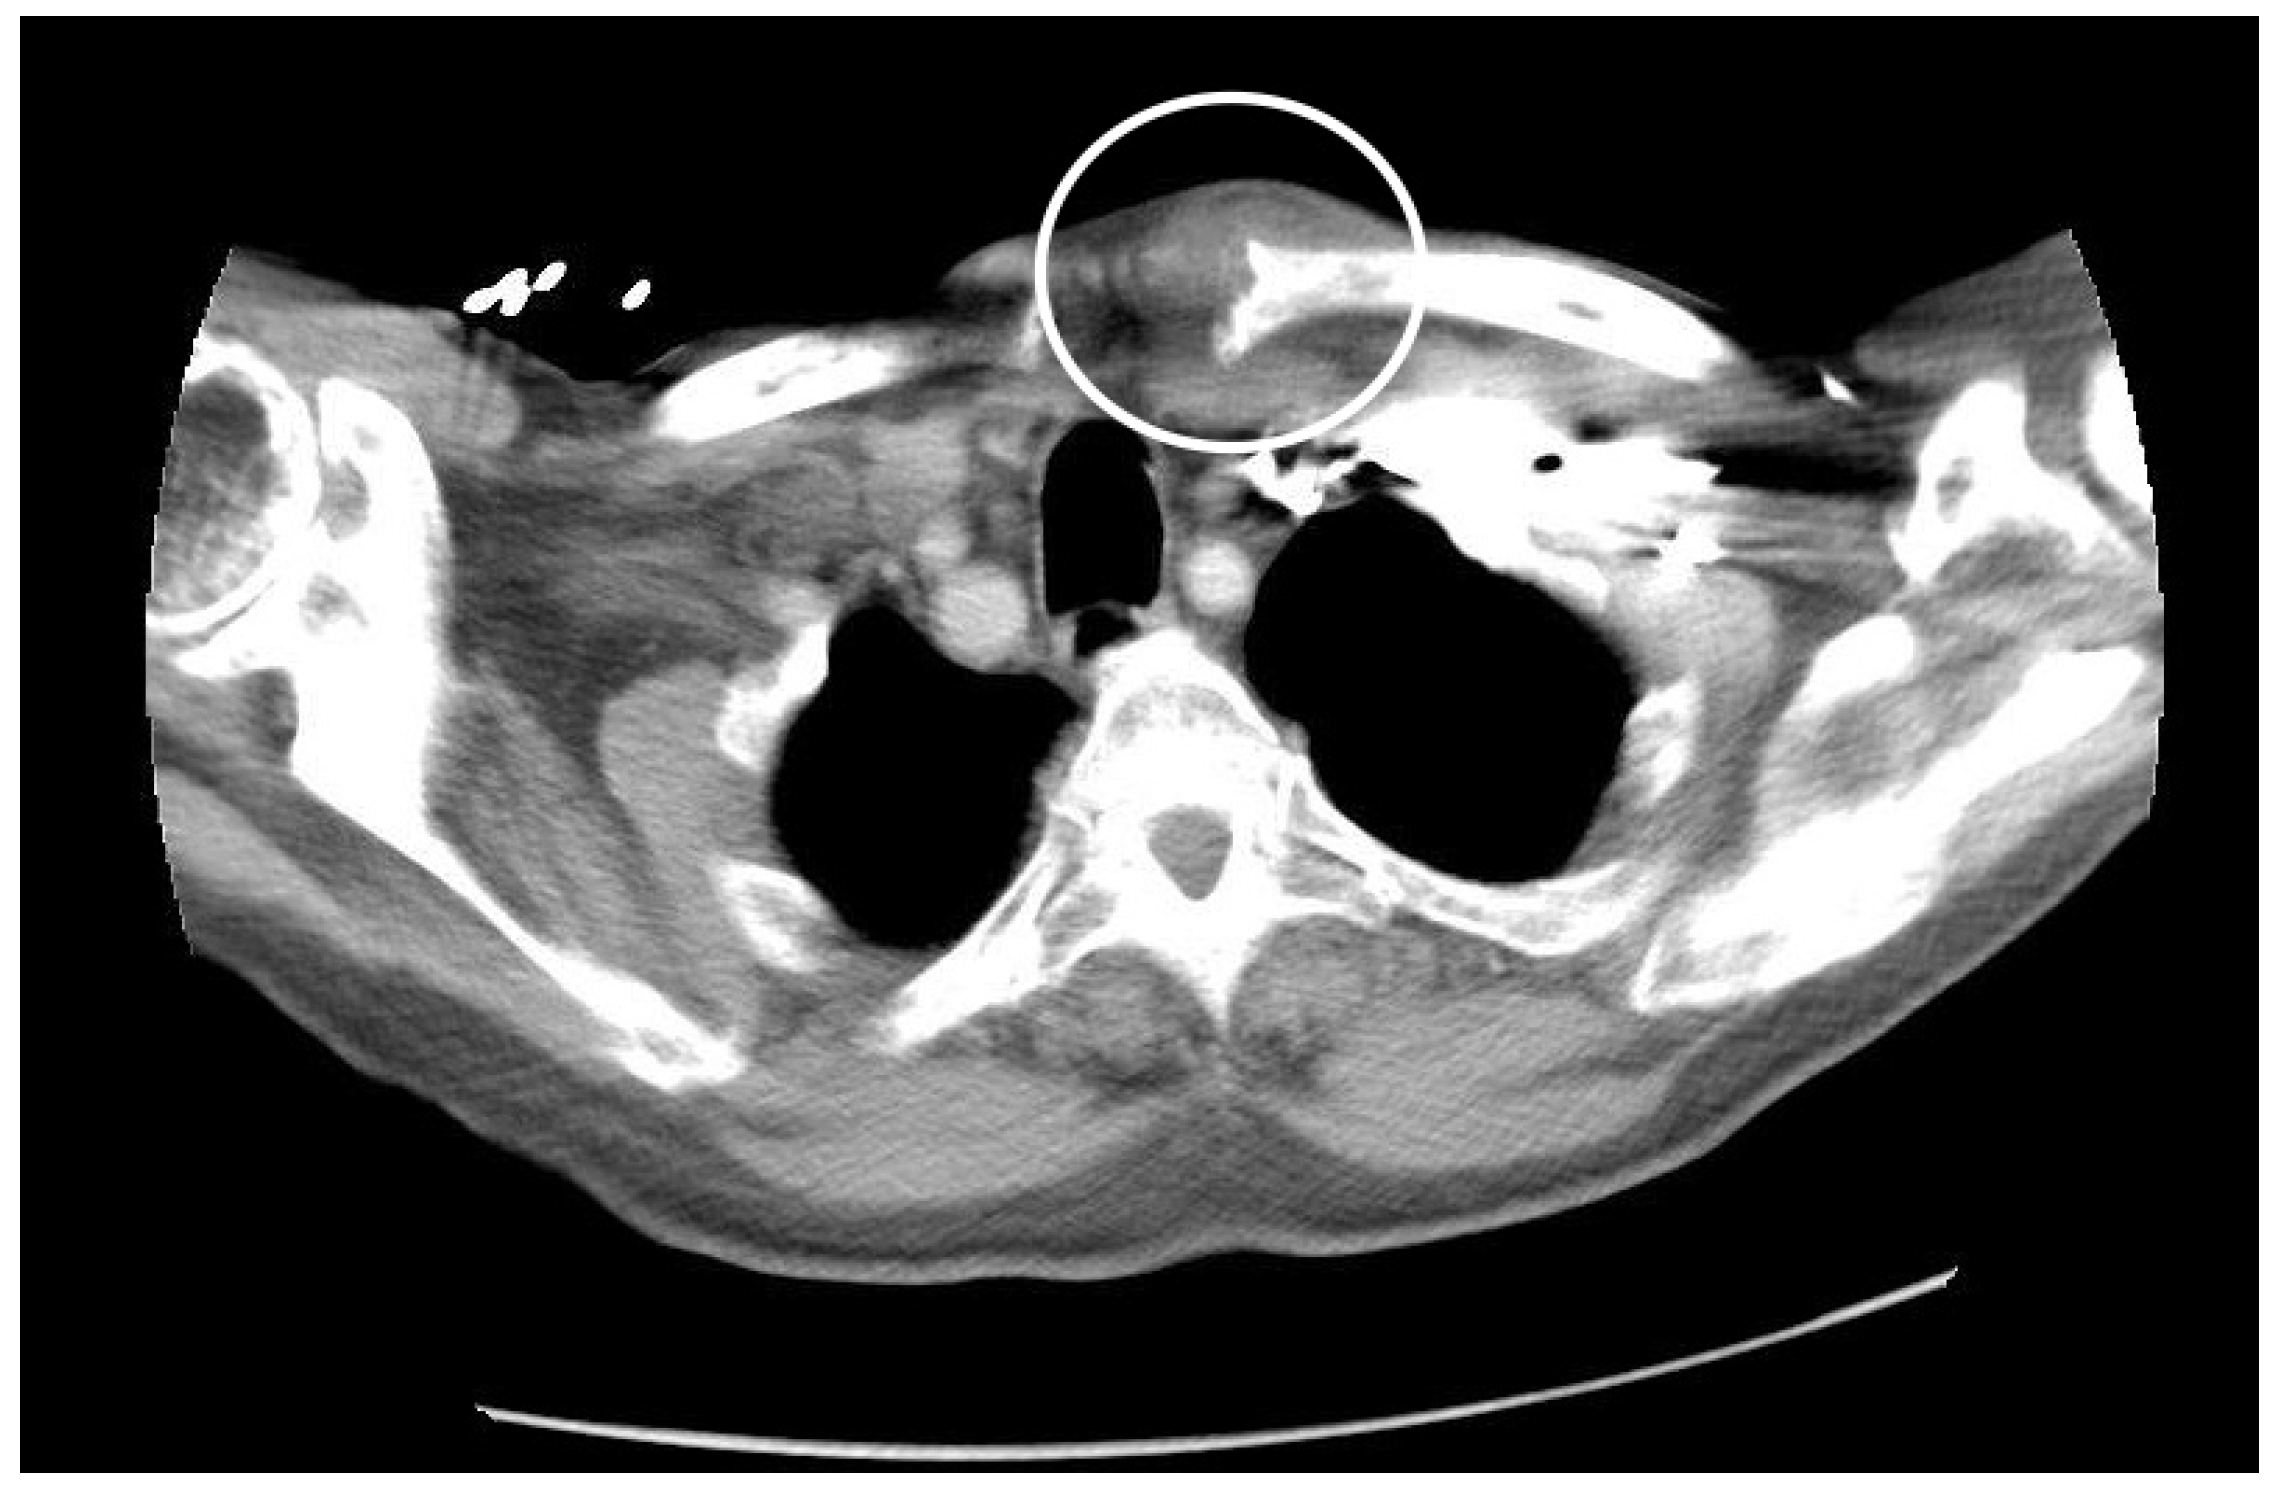

On hospital day one, blood and urine cultures yielded Gram-negative bacilli that were later identified as pan-susceptible E. coli. Mental status improved significantly on the second day of admission. On the third day of appropriate therapy, the patient continued to be febrile. His physical exam revealed a new finding of tenderness over the left upper sternal border associated with swelling and erythema, which was concerning for left SCJ septic arthritis (Figure 1). The patient also started to have new complaints of dysphagia and odynophagia on the third day as well.

Figure 1.

Overt appearance.